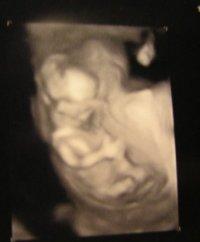

Endlich war es heute soweit - wir durfen unseren Bauchzwerg sehen Very Happy ..und ehrlich gesagt bin ich erleichtert, dass es erstmal bei einem bleibt Smile Unser Termin war erst nachmittags und ich war den ganzen Tag total aufgeregt und musste noch mehr auf's Klo rennen als sowieso schon Confused zum Glück war bei der Arbeit relativ viel los, so dass ich ganz gut abgelenkt war. Als es dann aber endlich soweit war liefen mir direkt ein paar Tränchen herunter....es war einfach so schön dieses Menschlein zu sehen. Der Zwerg hatte es sich ganz gemütlich gemacht und uns direkt "den Daumen hoch " gegeben Laughing Allgemein war er/oder sie etwas schüchtern - mit abgewandtem Gesicht und im Schneidersitz. Ganz anders als Leto, der bei diesem ersten US mit gespreizten Beinen auf dem Kopf stand und Breakdance geuebt hat Laughing Ich durfte dann auch ein paar Mal Husten und herumlaufen um den Kleinen zu etwas Bewegung zu animieren - und tatsächlich haben wir ihn dann noch von vorne gesehen. Ich habe mal ein Photo angehängt. Alle Werte waren super und entwicklungsgerecht . Die Herzaktivität war vorbildlich, zwei Hände und Füße waren klar zu sehen, alle Risikowerte für Down-Syndrome usw sind auch niedrig. Insgesamt durften wir ca 20 Minuten gucken und haben eine DVD die jetzt auf hot Rotation läuft Smile Morgen wollen wir sie auch mal Leto zeigen. Ganz liebe Grüße und weiterhin fröhliches Kugeln -Kiwi

Das Bild ist ja super! Schön, dass alles ok ist. Wollt Ihr wissen, was es wird? LG